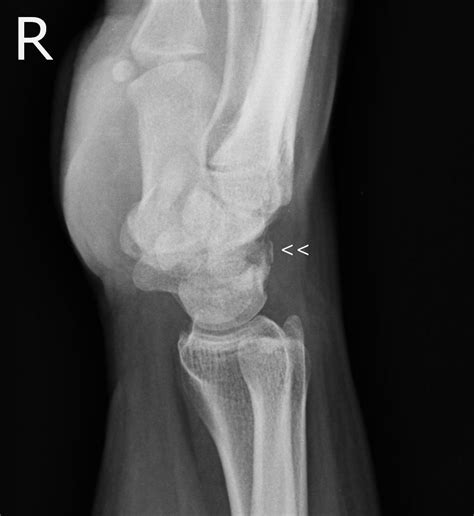

The triquetrum is a pyramidal-shaped bone located on the ulnar side of the wrist, just distal to the ulna. It articulates with the lunate bone, the hamate bone, and the triangular fibrocartilage complex (TFCC). Because of its unique anatomical position, a fracture triquetral bone often occurs at the dorsal aspect of the bone. These fractures are typically classified as either an avulsion fracture—where a small piece of bone is pulled away by a ligament—or a body fracture resulting from direct trauma.

X-ray The primary tool for viewing bone breaks, though lateral views are often needed for the triquetrum.